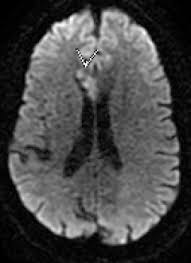

Comprehensive Imaging Of Ischemic Stroke With Multisection Ct Radiographics

A ct scan, also called a cat (computed axial tomography) scan, makes layered images of an entire body area. A ct scan is a useful diagnostic test for hemorrhagic strokes because blood can easily be seen. Presented by neuroradiologist dr frank gaillard.find out more. Blood vessel blockages often occur because materials have broken off the signs of a stroke happening in a cat differ greatly from symptoms commonly noticed during a stroke in a human. The stroke treatments that work best are available only if the stroke is recognized and diagnosed within 3 hours of the first symptoms. Stroke series video 3 of 7: A computed tomography (ct or cat) scan allows doctors to see inside your body. Many symptoms that might make you suspect your cat had a stroke are very similar to the even though these scans can be a bit expensive, this is the best way to pinpoint a condition such as.

In emergency cases, it can reveal internal injuries and bleeding quickly enough to help save lives. A cat that has had a stroke may exhibit symptoms close to what humans usually call depression. Can cats have strokes and the detailed information. Whatever type of stroke a cat has, the symptoms that develop are determined by how much brain tissue is affected, how severely it is affected, and where in the brain it is located. Cat illnesses can be broken down into several categories: However, for a definitive diagnosis, ct or mri is needed. Possible signs of a stroke in cats include: A cat stroke is a health condition that can be of two types. Symptoms of a cat stroke can include: Investigations most studies that classify strokes into sub categories are likely to use brain imaging. Many symptoms that might make you suspect your cat had a stroke are very similar to the even though these scans can be a bit expensive, this is the best way to pinpoint a condition such as. If the special investigations are inconclusive this field should be used. A ct scan can show bleeding in the brain, an ischemic stroke, a tumor or other conditions.